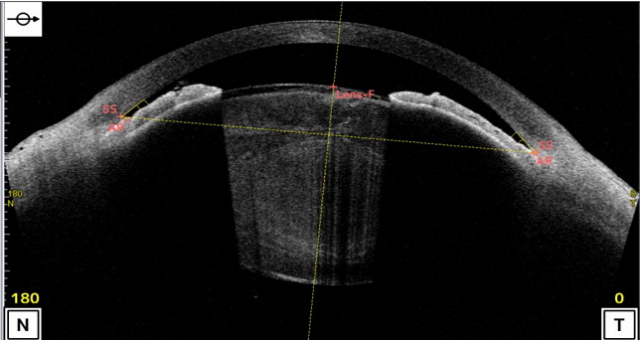

투명도가 상실된 과숙형 백내장(위)과 방수 유출로가 거의 막힌 폐쇄우각 상태. 이안과 제공 투명도가 상실된 과숙형 백내장(위)과 방수 유출로가 거의 막힌 폐쇄우각 상태. 이안과 제공

그러나 요즘 비교적 젊은 40~50대에서도 알 수 없는 원인에 의해서 백내장이 발생하는 경우도 있다. 특히 어떤 약물이나 전신질환, 스트레스 등에 의한 눈 속 산화적 손상에 의해 수정체가 팽창되면서 과숙형 백내장이 발생하고, 눈 속 공간(전방각)이 좁아지는 폐쇄각 녹내장으로 진행되는 경우도 있어서 백내장 수술을 빨리 해야 하는 경우도 있다.

이안과 최봉준 원장은 “질문 속 환자는 나이가 들면서 수정체는 점점 팽창되고 눈 속 공간이 막혀서 눈 내부에 영양분을 공급하는 방수가 배출되지 못해서 발생하는 급성폐쇄각 녹내장이 있었고, 그로 인해 이차적인 백내장이 발생한 것으로 생각된다”고 말했다.

이런 경우 백내장 수술을 하면 팽창된 백내장이 제거되고 얇은 인공수정체가 삽입돼 시력 개선뿐 아니라 눈 속 공간이 깊어져 방수의 유출이 잘 되어 녹내장의 치료 효과도 얻을 수 있는 경우가 많다.